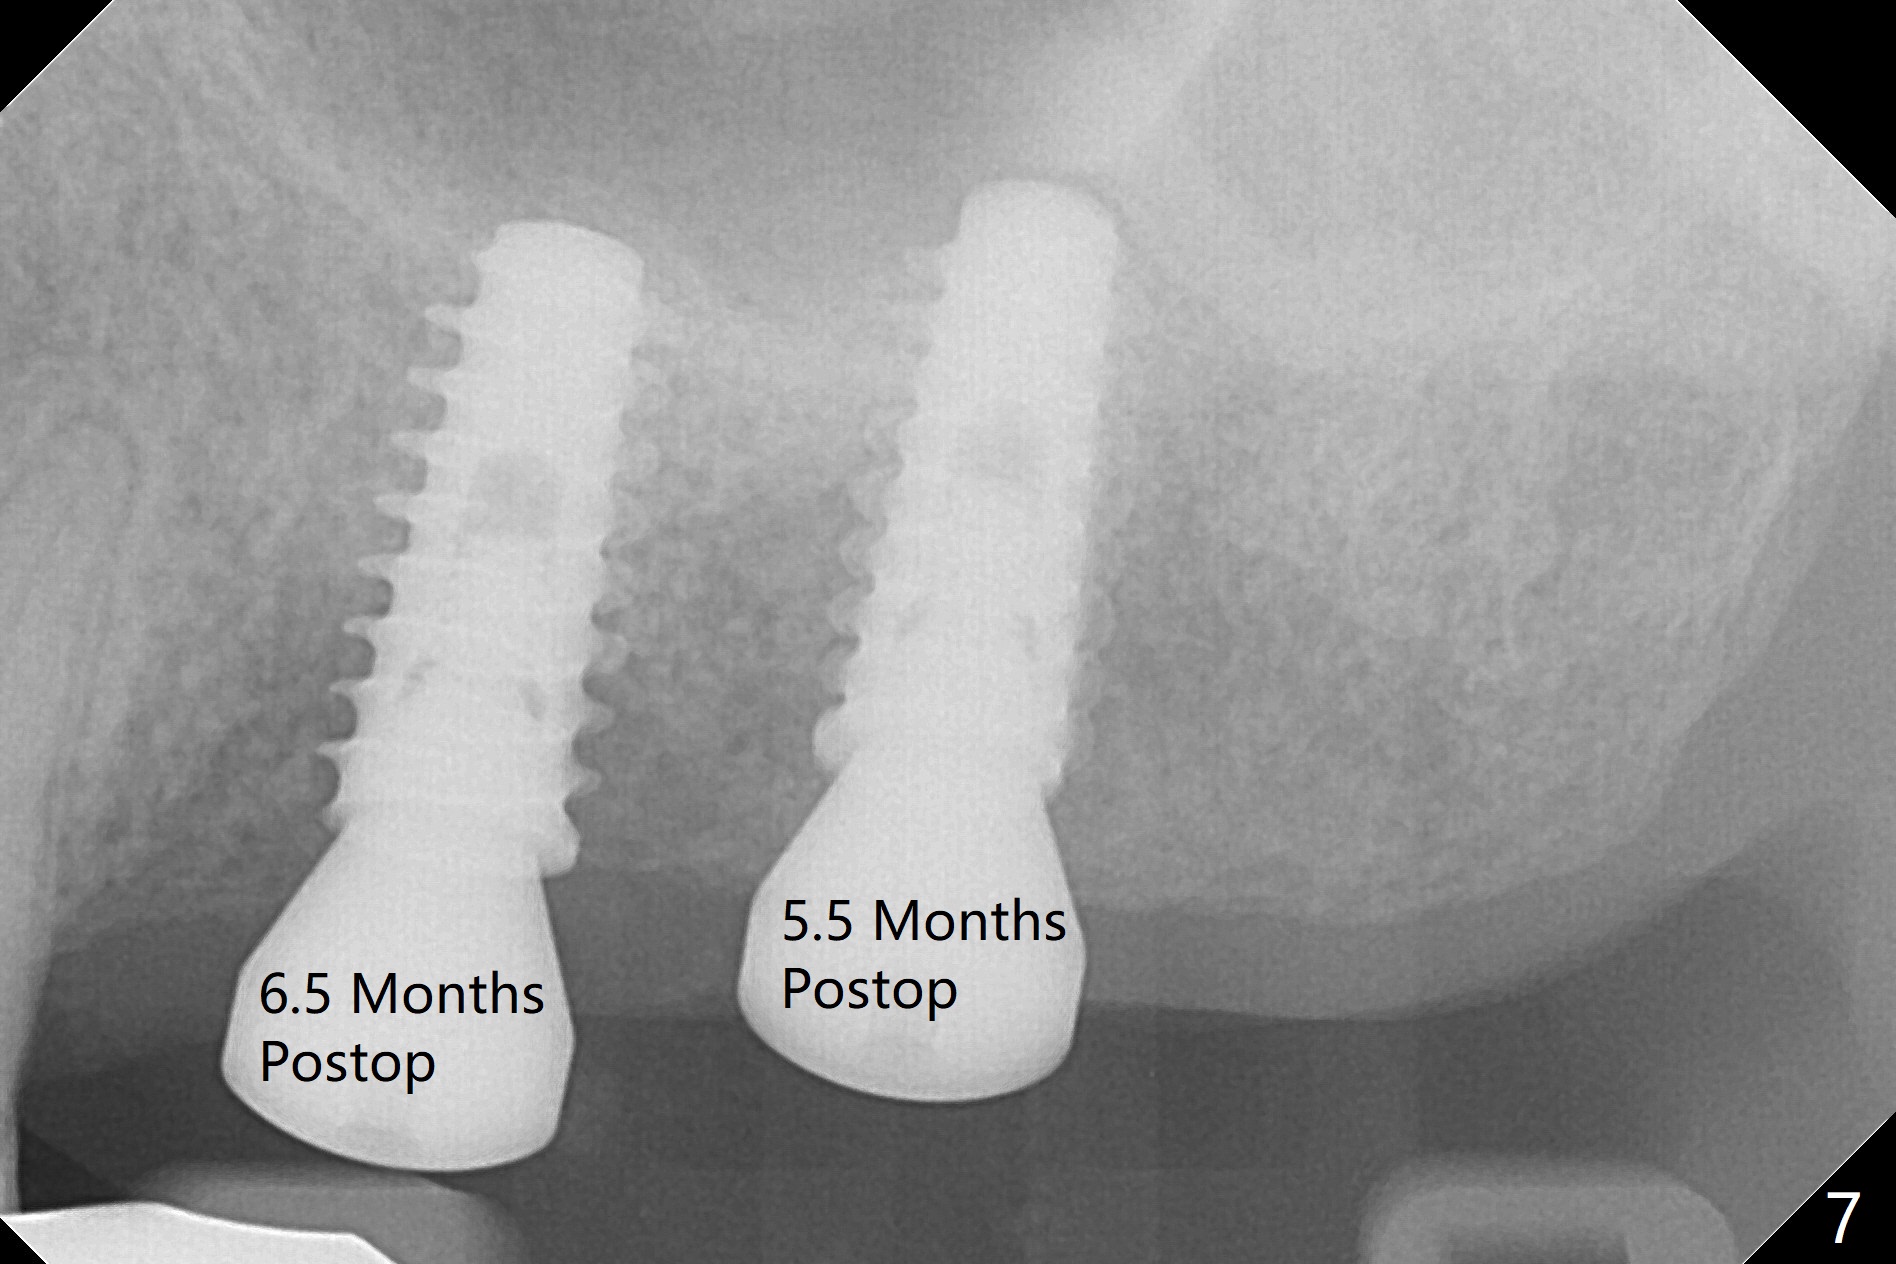

The ridge over the mobile tooth #14 is wide, suggesting bruxism pathogenesis (Fig.1). In spite of calculus over the roots of the extracted tooth (Fig.2), the septum remains. Osteotomy is initiated in the palatal slope of the septum (Fig.3,3' red dashed line). A 4.3 mm Magic Drill (MD) cannot bite into the bone probably because of the slope. Sequential osteotomy has to be done, starting with the smallest MD until 4.8 mm one. A 5x9 mm dummy implant is placed with 50 Ncm (Fig.4). To place 5x11 mm IBS implant (Fig.5), 5.3 mm MD has to be used; prior to implant placement, sinus lift is accomplished with mixture of autogenous bone and Vanilla graft (white *); more allograft (black *) is placed around the implant before insertion of a 6x5.7(3) mm abutment. More allograft is placed around the abutment (Fig.6 *) prior to an immediate provisional fabrication. The grafted bone appears to become the native bone, although at the low density, 6.5 months postop (Fig.7). The implant at #14 appears to have been placed in the middle of the alveolus buccopalatally (Fig.8).